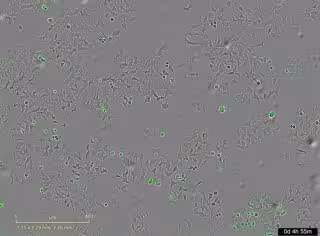

La imagen representa las células de cáncer muertas al activarse su proteína de membrana PAR-1 por la proteasa bacteriana HapA.

El estudio, publicado en la revista 'Cell Death Discovery', ha mostrado cómo la proteína HapA, producida por la mencionada bacteria, actúa como una "llave" capaz de localizar unas "cerraduras" específicas, conocidas como receptores PAR-1 y PAR-2, que se encuentran en la superficie de las células tumorales y que, al abrirlas, se provoca una reacción en cadena dentro de las células que las lleva a autodestruirse.

Durante el proceso, se han empleado sistemas avanzados de imagen en tiempo real que permiten contar células vivas y muertas, y medir la apoptosis para observar con precisión el bloqueo de las vías. La investigación ha recibido financiación del Consejo de Investigación Sueco, la Sociedad de Cáncer de Suecia, la Unión Europea y la Universidad de Umea (Suecia).